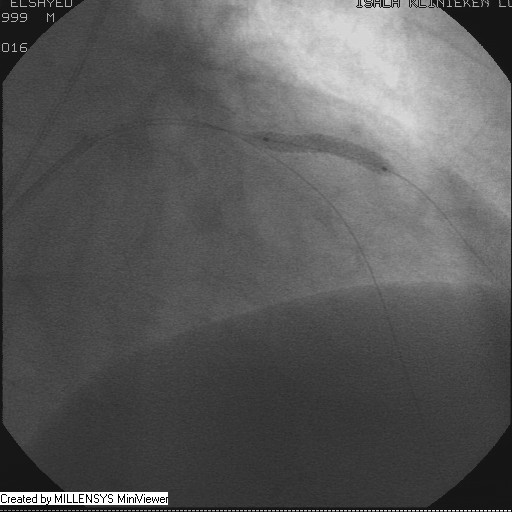

Patient transfered to Cardiac Catheterization Laboratory, coronary angiography showed atherosclerotic coronaries but without significant lesions, especially LAD that was patent with TIMI 3 flow (Figure 1- 5). Re-evaluation of the Angiography showed a small stump that can be for an occluded 1st diagonal (Figure 2a), at that level the LAD has a non-significant lesion.

Figure 2

Figure 2A